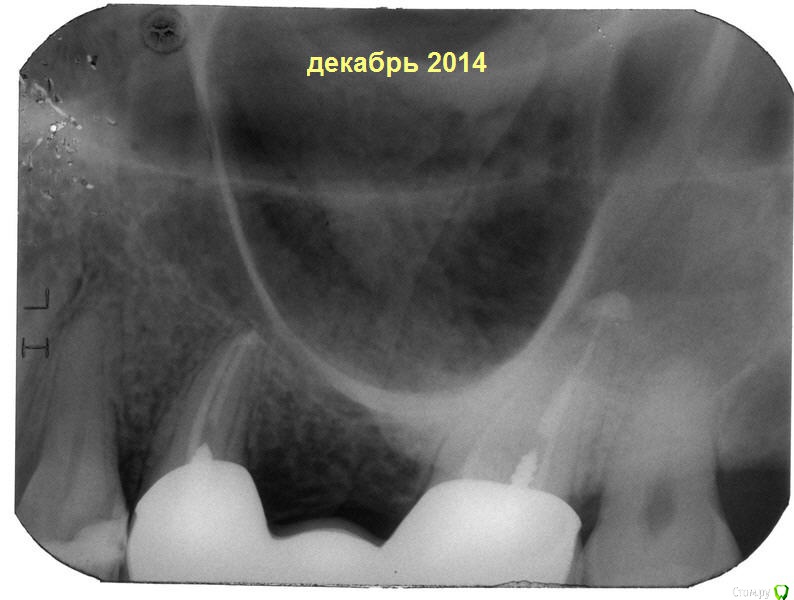

vadim240283 Опубликовано 8 декабря, 2014 Поделиться Опубликовано 8 декабря, 2014 (изменено) Здравствуйте!История такая: год назад поставил мосты с двух сторон на 5 и 7 зубы. Все было хорошо, но 1,5 месяца назад при чистке промывной части суперфлосом появилась кровь с неприятным запахом. Погрешил на десны, купил пасту для десен, пользовался месяц - без изменений. 2 недели назад опухла десна в районе 5 зуба, неприятный запах не исчезал даже после чистки и полоскания. На следующее утро десна опухла еще больше, жевать и улыбаться было больно. Потрогал мост, а он шевелится вверх-вниз и вправо-влево где-то на 1-0,5 мм. Шевелится точно, проверял мост с другой стороны - держится как влитой. Так как предстоящий день обещал быть насыщенным, а ноюще-пульсирующая боль была ни к чему, принял Нимесил. В 17:00 того же дня посетил протезиста, вот только к тому моменту опухоль почти сошла.Диагноз: травмирование десны суперфлосом или рыбной косточкой, протез шевелится потому что десна воспалена.Рекомендации: полоскания.На третье утро десна опухла так, что перекрыла половину протеза, боль, кровь, запах. В вечеру опять полегчало. Четвертый день прошел аналогично. Последние 1,5 недели десна не опухала, но шевеление протеза и кровоточивость десны остались. Боюсь, что гниет зуб. Что за светлые сгустки у корней 5 и 7? Помогите советом! Благодарю!http://s019.radikal.ru/i609/1412/0c/f5542fcf6961t.jpg Изменено 8 декабря, 2014 пользователем vadim240283 Ссылка на комментарий

chervoncevdaniil Опубликовано 14 января, 2017 Поделиться Опубликовано 14 января, 2017 (изменено) Уважаемый Вадим,в 2014 вам доктор посоветовал снять мост.Если бы вы это сделали зуб можно было спасти,потому что на снимке 14 года состояние костной ткани было нормальным,сейчас там дефект таких размеров,что теперь только под удаление+дефект костной ткани у соседнего зуба,причиной которому является опять же воспаление у опоры этого моста.Зачем создавать темы,спрашивать советы и все равно ничего не делать? Изменено 14 января, 2017 пользователем chervoncevdaniil 3 Ссылка на комментарий